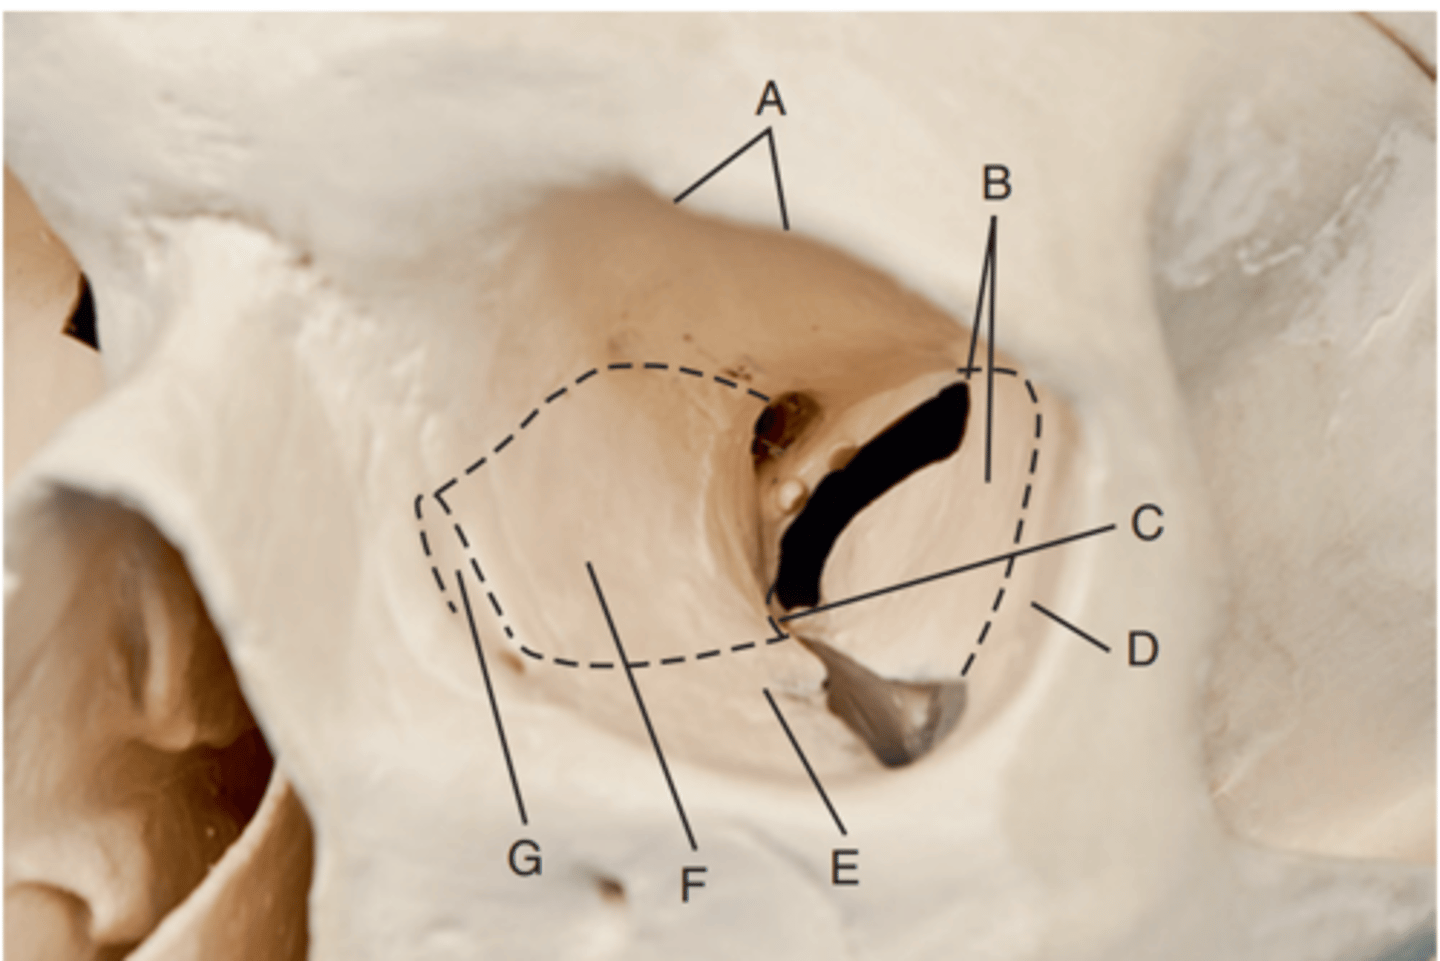

Optic foramen

Label A

Sphenoid strut

Label B

Superior orbital fissure

Label C

Inferior orbital fissure

Label D

Orbital plate of frontal bone

Label A

Sphenoid bone

Label B

Optic foramen and canal

Label C

Superior orbital fissure

Label D

Infraorbital margin (IOM)

Label E

Sphenoid strut

Label F

Lateral orbital margin

Label G

Supraorbital margin

Label H